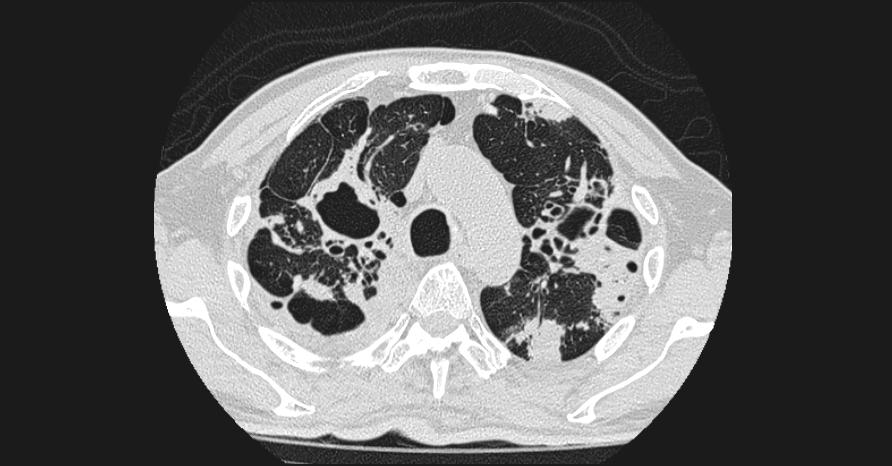

La tomografía de tórax contrastada demostró distorsión difusa de la arquitectura pulmonar secundaria a múltiples áreas de consolidación alveolar bilateral, asociadas a patrón de árbol en gemación y múltiples cavitaciones pulmonares. Destaca la presencia de una cavidad en el lóbulo superior izquierdo que contiene una lesión nodular intracavitaria compatible con bola fúngica, hallazgo sugestivo de aspergiloma desarrollado sobre cavidad pulmonar previa.

Además, se identificó derrame pleural derecho, neumotórax apical derecho probablemente secundario a ruptura cavitaria y cambios pulmonares crónicos compatibles con enfisema, con afectación estimada del 40–50% del parénquima pulmonar.

Los hallazgos en conjunto son altamente sugestivos de tuberculosis pulmonar difusa activa complicada con colonización fúngica intracavitaria, entidad que incrementa el riesgo de hemoptisis y deterioro respiratorio progresivo, por lo que se recomienda correlación microbiológica y manejo especializado oportuno.